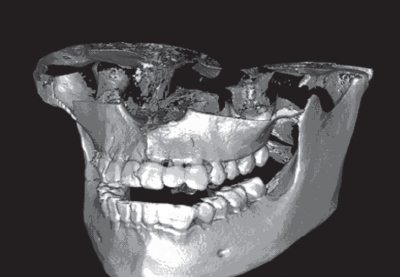

Рис. 2. Трехмерная графика при обработке цифрового изображения нижнего отдела лица

Применение трехмерной графики при обработке цифровых изображений позволяло получить объемную картину изучаемых областей. Полученные рельефные изображения исследуемых объектов делают их более информативными и привычными для восприятия (рис. 2).